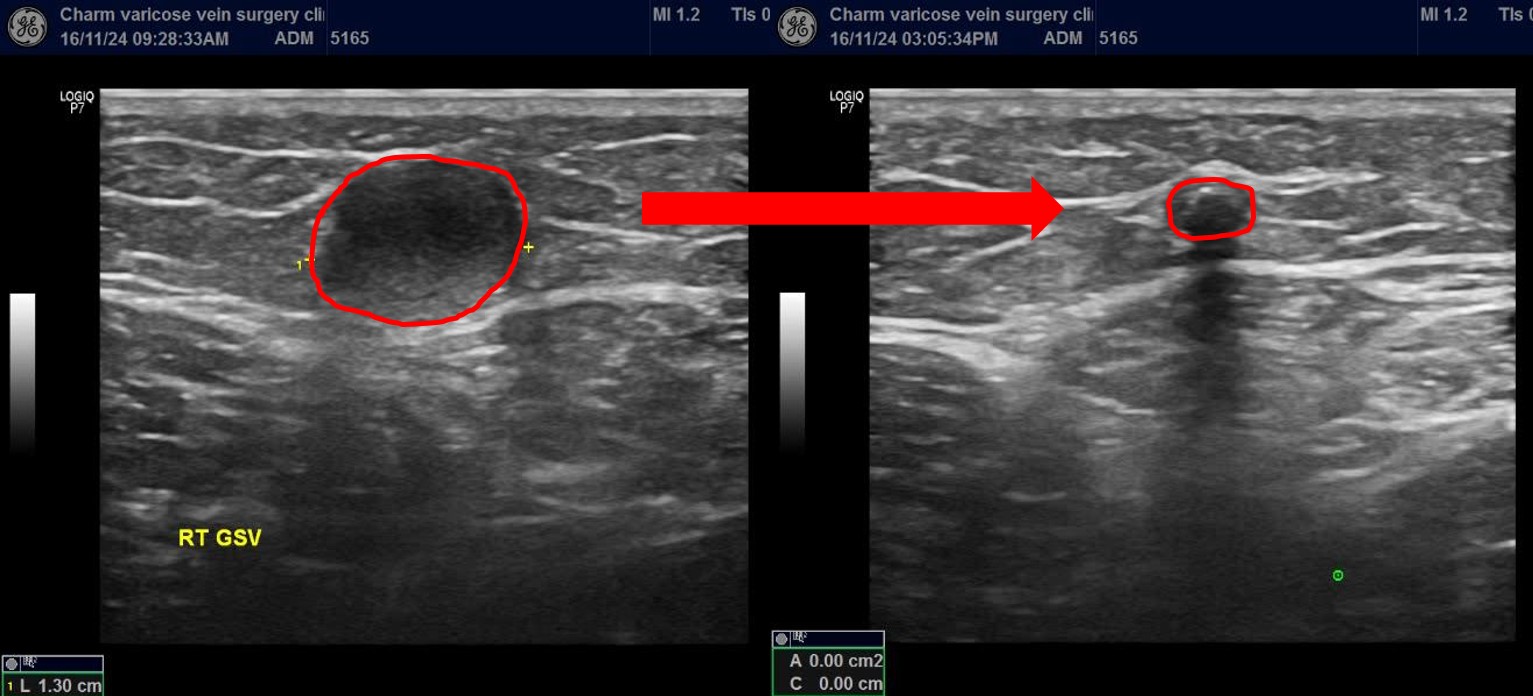

마찬가지로 약 1.3cm 가량의 큰 직경의 혈관이

수술 직후 6시간뒤 바로 유착되어 막힌 것이 확인됩니다